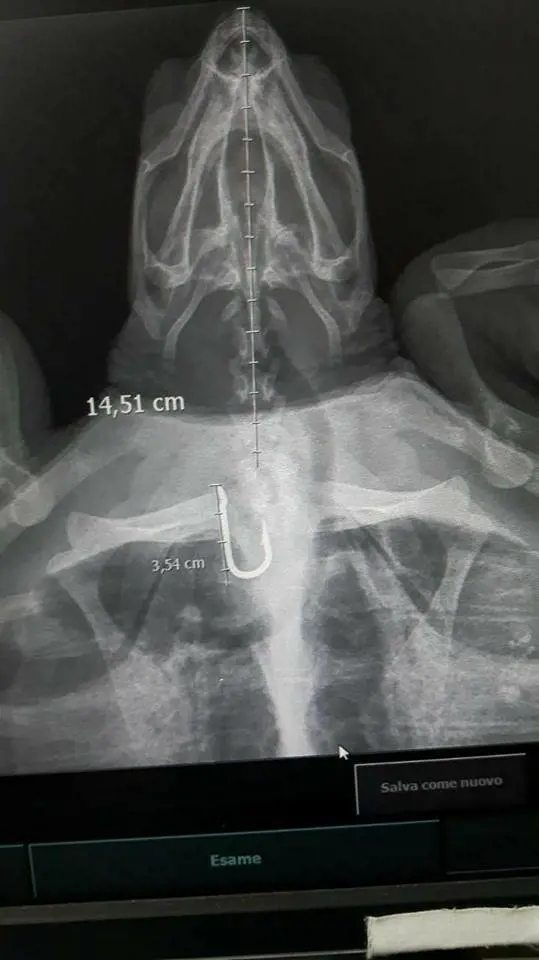

Napoli, salvata tartaruga che aveva ingerito un amo

L'animale è stato trovato da un sommozzatore a Gaeta ed è stato operato nel centro ricerche della stazione zoologica di Napoli "Anton Dohrn"